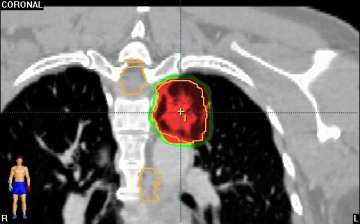

Stereotactic Body Radiation Therapy (SBRT) is a treatment procedure similar to central nervous system (CNS) stereotactic radiosurgery, except that it deals with tumors outside of the CNS. A stereotactic radiation treatment for the body means that a specially designed coordinate-system is used for the exact localization of the tumors in the body (Figure 1) in order to treat it with limited but highly precise treatment fields. SBRT involves the delivery of a single high dose radiation treatment or a few fractionated radiation treatments (usually up to 5 treatments). A high potent biological dose of radiation is delivered to the tumor, improving the cure rates for the tumor, in a manner previously not achievable by standard conventional radiation therapy (Figure 2).

Similarly, because this specialized form of radiation involves the use of multiple radiation beam angles, expert Radiation Oncologists specialized in this technique are able to safely deliver high doses of radiation, with very sharp dose gradient outside the tumor and into the surrounding normal tissue (Figure 3).